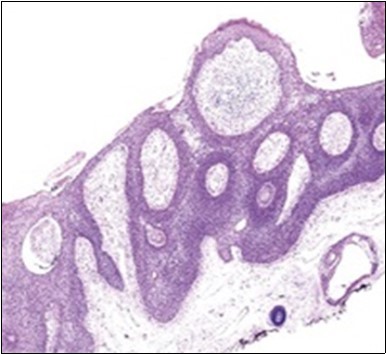

Granular arrangement of malignant cells and intercellular bridges are conspicuous with the demonstration of nuclear atypia, pleomorphism, prominent mitosis and tumour necrosis. A peripheral palisade is discernible within the cellular aggregates. Mitotic figures are common and can be quantified as up to 12 mitosis/ high power field. Tumour differentiation can prominently be of the ductal category with the demonstration of intra-cytoplasmic lumina. Comedo type tumour necrosis is evident along with foci of squamous differentiation The neoplasm is reactive to periodic acid Schiff ‘s (PAS) stain. (Figure 1, Figure 2, Figure 3, Figure 4, Figure 5, Figure 6, Figure 7, Figure 8, Figure 9, Figure 10, Figure 11, Figure 12, Figure 13.

Figure 1.Solid aggregates of tumour cells and duct structures in eccrine porocarcinoma (14).

Figure 2.Epidermal projections lined with atypical and malignant epithelial cells in eccrine porocarcinoma (14).

Figure 3.Cohesive accumulations with numerous ductular articulations of carcinoma cells in eccrine porocarcinoma (15).